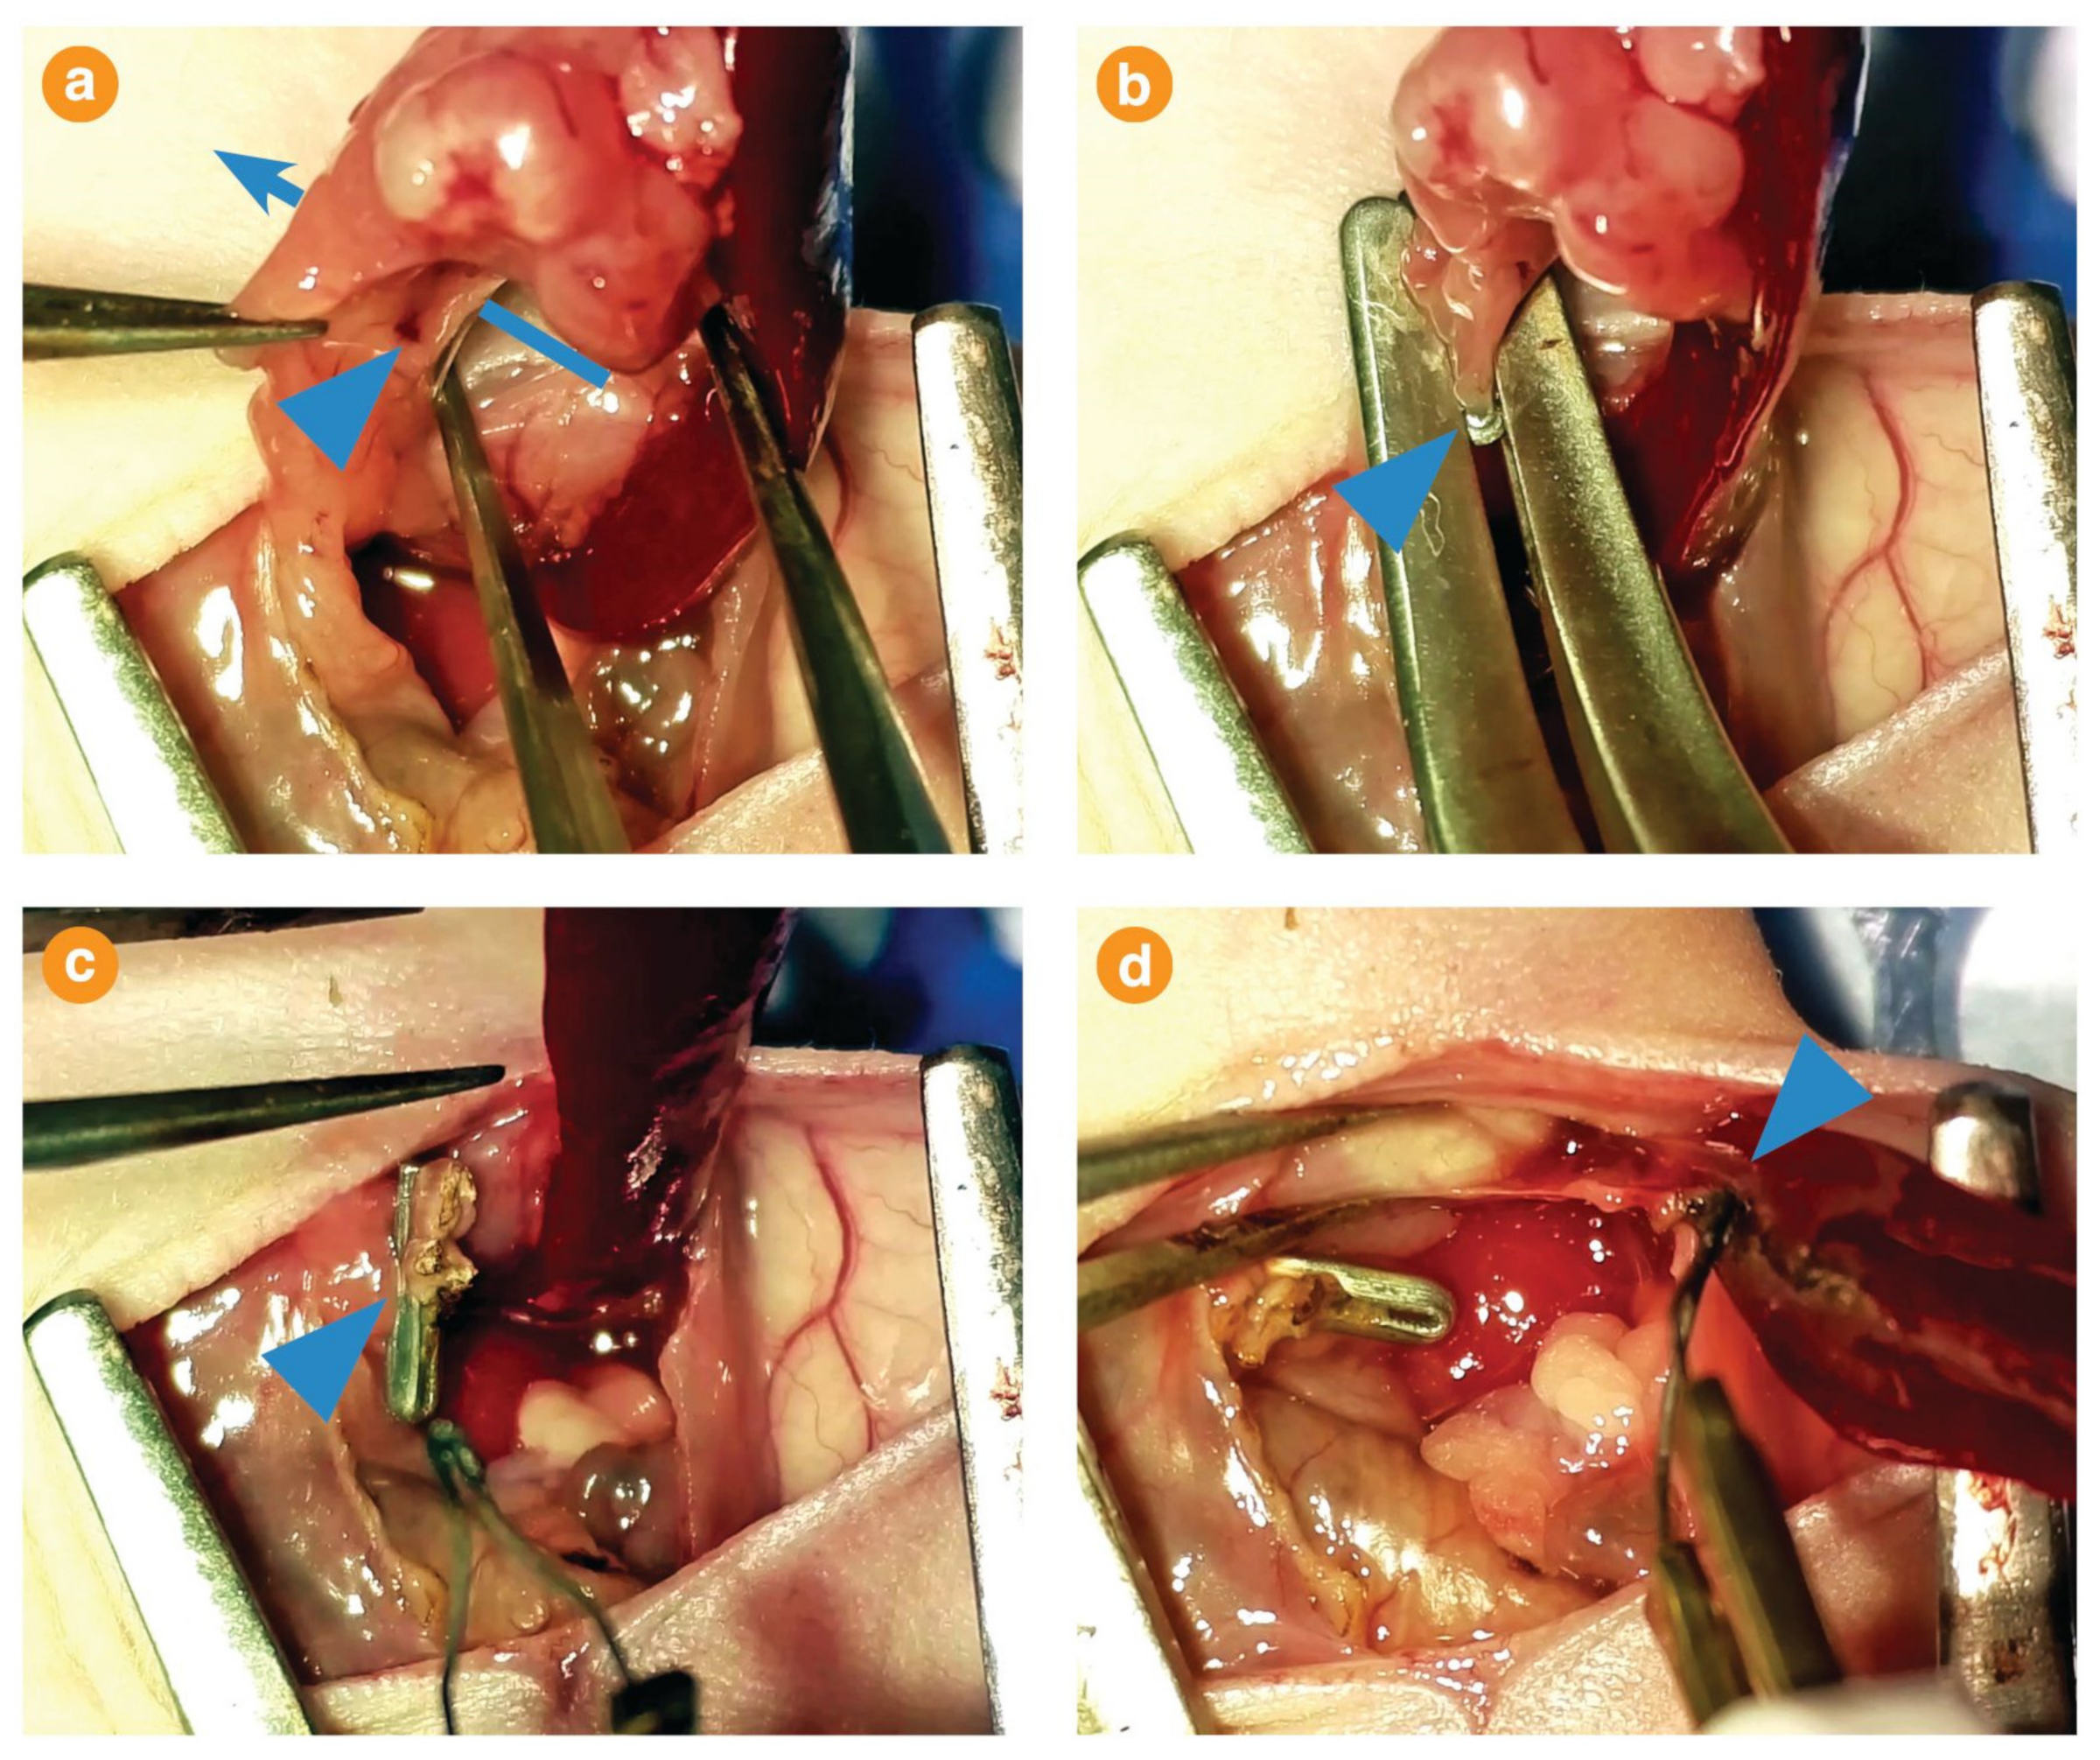

2.3. Tumour Resection

Appendix A.2. Tumour Implantation

Appendix A.3. Tumour Resection